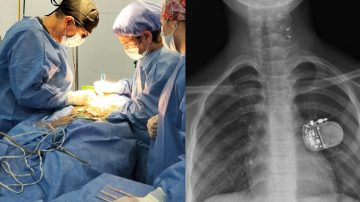

Interior Por primera vez en la historia de Sumampa, se realizó una cirugía en el hospital público 27 noviembre, 2025